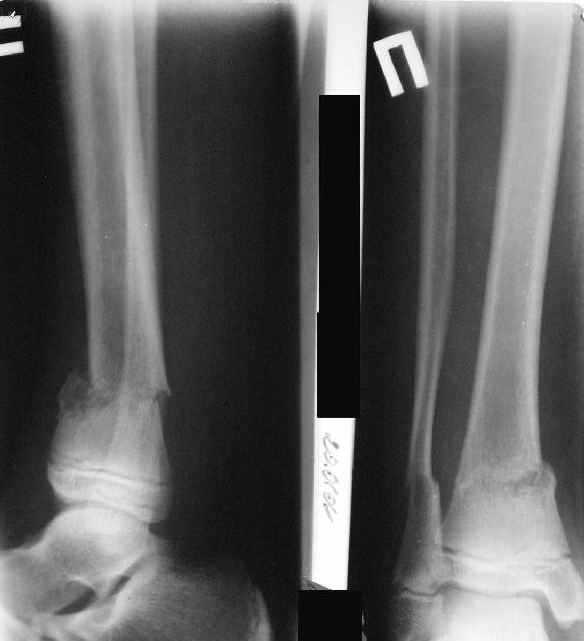

A> Перелом костей н\3 правой голени со смещением.

Это от 13.10.04? А это близкие к первичным снимки?

A> Перелом большеберцовой

A> кости можно охарактеризовать как компрессионно-оскольчатый.

A> В январе 2005: варусная деформация н\3 голени,

Первичные

|